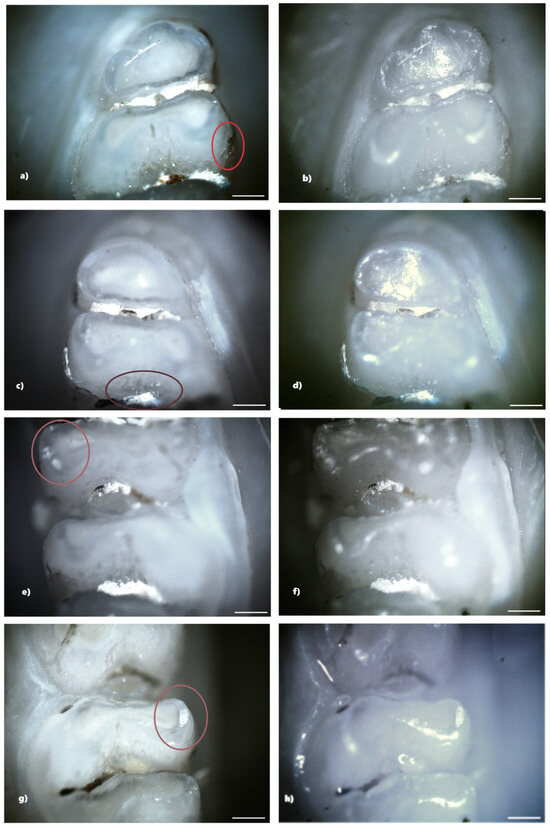

Figure 7. Demineralization on the occlusal surface of some molars (a,c,e—PLM image, cross polarizers, 4× objective; b,d,f—BFM image, 4× objective) and on the mesial surface of a molar (g—PLM image, cross polarizers, 4× objective; h—BFM image, 4× objective). Scale bar represents 500 μm.

In the standard dose ibuprofen group (8 mg/kg), 11 rats (73.33%) showed at least one clinical form of DDE. Of these, two rats showed hypoplasia and five rats showed demineralization. In addition, three rats showed both clinical forms of DDE. Within this group, from a total number of 240 teeth, 33 teeth (13.75%) presented at least one clinical form of DDE, respectively, 15 incisors (45.45%) and 18 molars (54.55%), and according to the clinical form of DDE, 7 teeth (21.21%) showed hypoplasia (molars) and 26 teeth (78.79%) showed demineralization (15 incisors and 11 molars). Each tooth with DDE had only one affected surface, resulting in a total of 33 affected tooth surfaces (Figure 7).